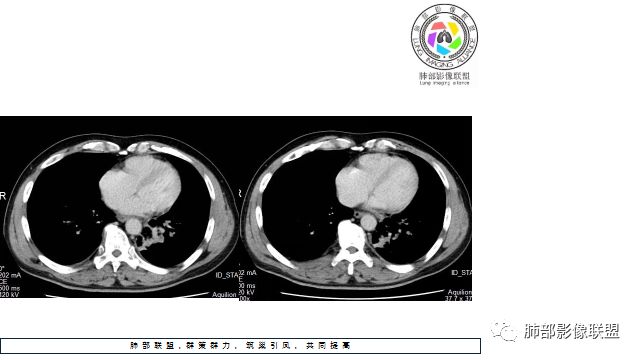

1.左下肺门区巨大肿块,支气管显示不清,轻度阻塞性炎症,没有明显肺不张,提示管腔受压狭窄可能性大于堵塞,这较少见于鳞癌。

2.病灶边缘光滑,未见明显分叶、毛刺,未见明显强化,这符合腺癌影像学特点,却符合神经内分泌癌表现。

3.病灶内密度均匀,轻到中度均匀强化,大病灶未见明显液化坏死区及空洞,不符合鳞癌而符合小细胞肺癌特点。

4.病灶内有肺动脉走形,血管局部受压,未见破坏,病灶乏血供,呈血管包埋或血管造影征;侵袭性力强及破坏力弱、血管漂浮都符合SCLC,所以鳞癌的可能性也不大。

5.左肺门块影或淋巴结肿大,竭力挤兑肺门血管结构,呈冰冻肺门;有时候SCLC可以单独呈现冰冻肺门,而没有没有冰冻纵隔。